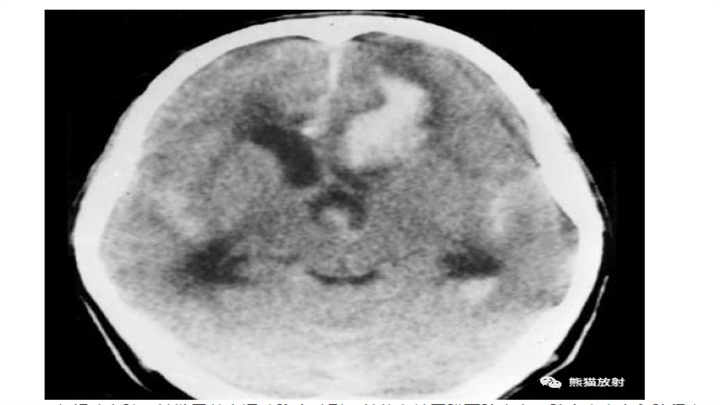

IPH随时间的演变。CT通常用于IPH随访中。上图为脑血肿患者在中风后数小时内的CT,注意病灶位置深,锯齿状边缘和小卫星灶的存在;中间图为14天后的CT,血肿体积缩小,密度减低,而周围水肿加重。下图为三个月后CT,病变被不规则低密度腔所取代,负占位效应,同侧侧脑室轻微扩张。